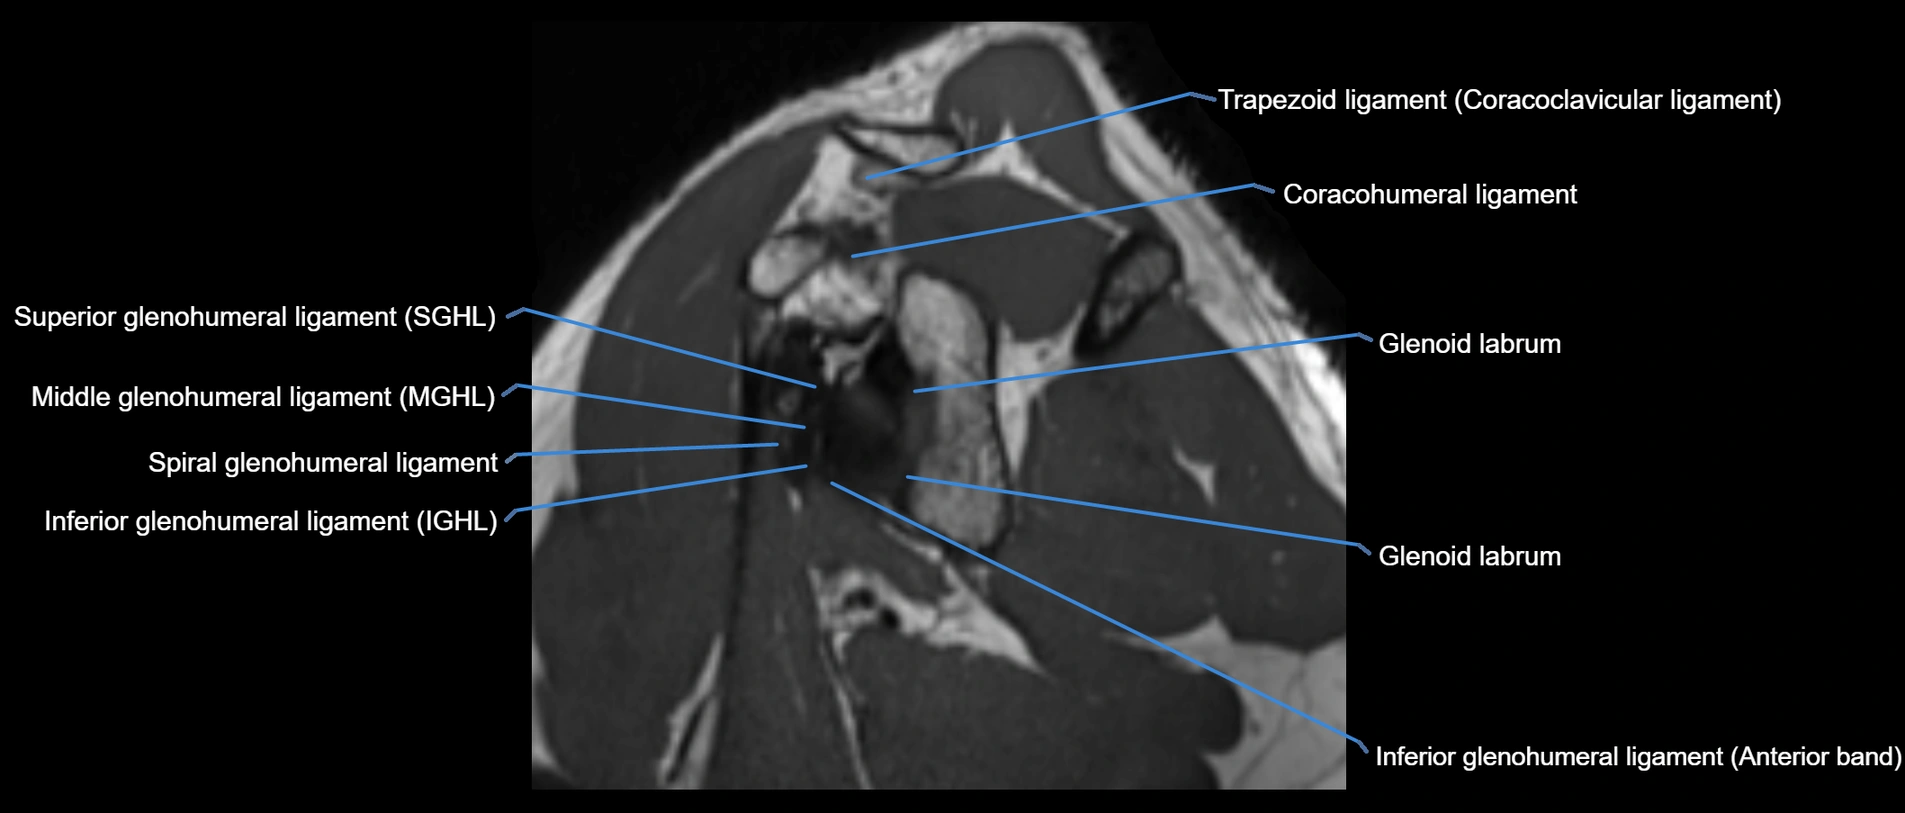

MRI images

image